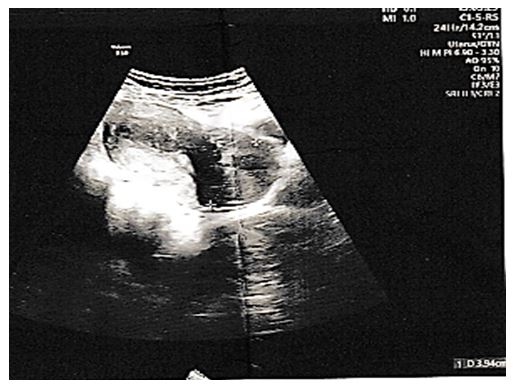

The history of the disease dates back to 2 years earlier marked by menometrorrhagia, with a history of multiple transfusions (a previous hemoglobin level of 4 g/dl) and a long history of taking progestogens without any notable effects. The patient was admitted for the purpose of hemodynamic stabilization with exploration of the symptoms, the ultrasound of the pubic area found a voluminous cervical mass of 3*4 cm.